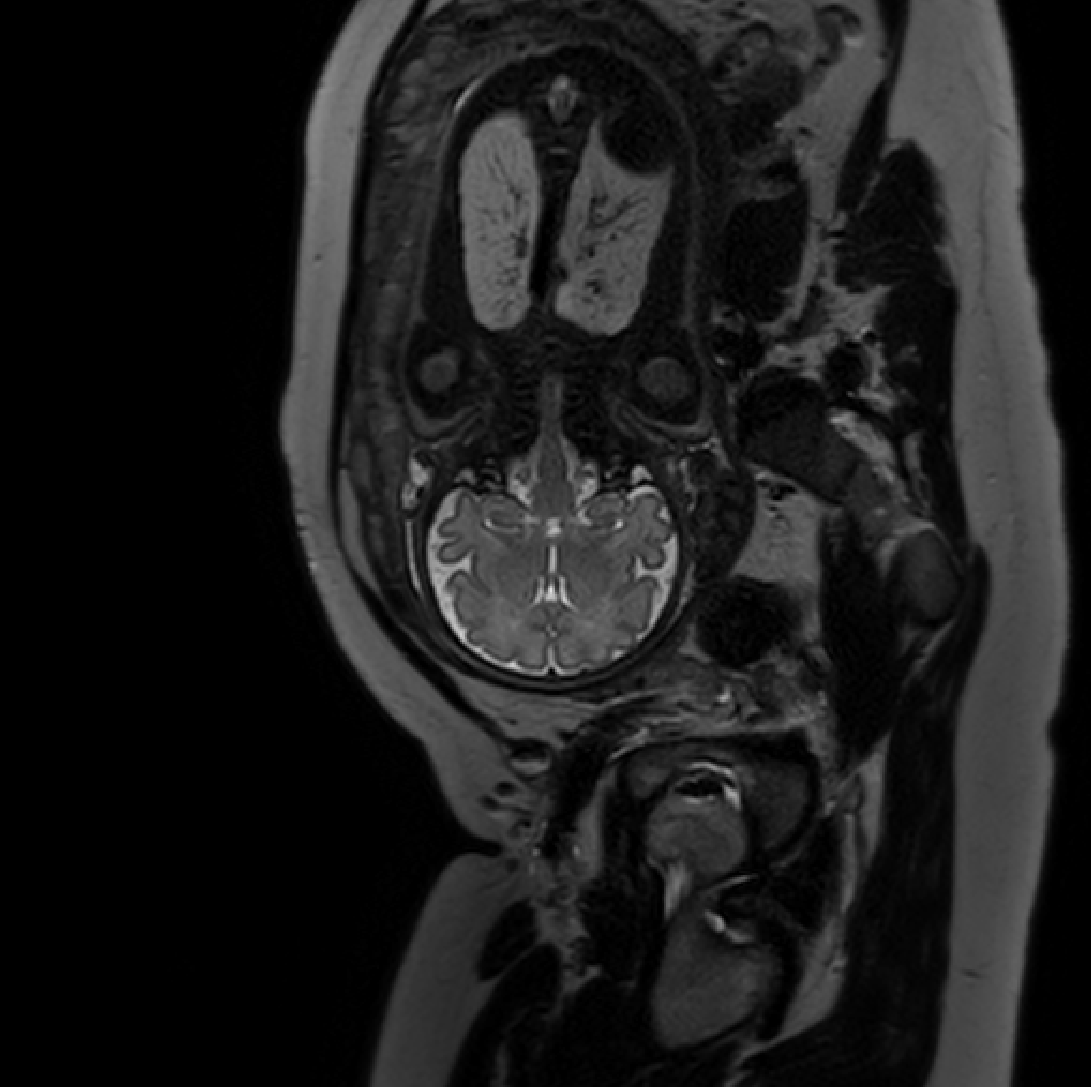

Table 1 lists average of quantitative evaluation results of these experiments and Figure 2 shows results obtained from each image. Figure 3 shows examples of the obtained segmentations.

Refer to caption

Figure 3: Example of ICV segmentations in images acquired in axial (left), coronal (middle) and sagittal (right) planes. Top row: A slice from T2-weigted image; Second row: Automatic segmentations obtained using 7 training images from the representative imaging planes; Third row: Automatic segmentations obtained using all 21 training images from all 3 image orientations; Bottom row: Manual segmentation.